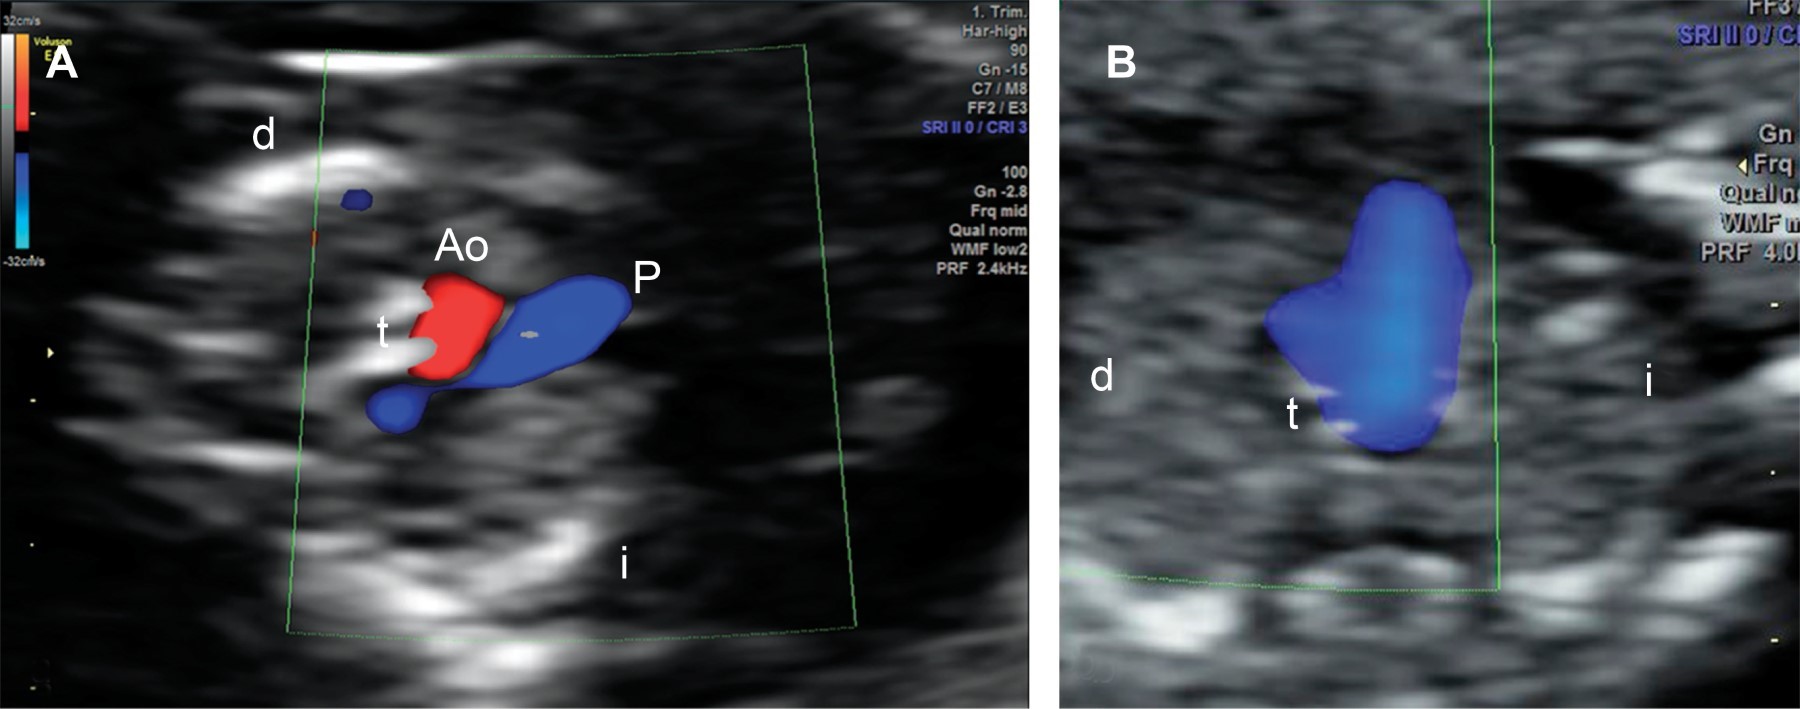

En la revisión cardiaca el corte axial de cuatro cámaras se observó anormal por ausencia de llenado del ventrículo izquierdo con Doppler color (Figura 1) y atresia mitral. En el tracto de salida izquierdo se identificó atresia aórtica y ausencia de flujo anterógrado. En el corte de tres vasos y tráquea se identificó la imagen en "V" con flujo reverso a través del istmo aórtico (Figura 2). Con estas características se integró el diagnóstico de SVIH.

Figura 1